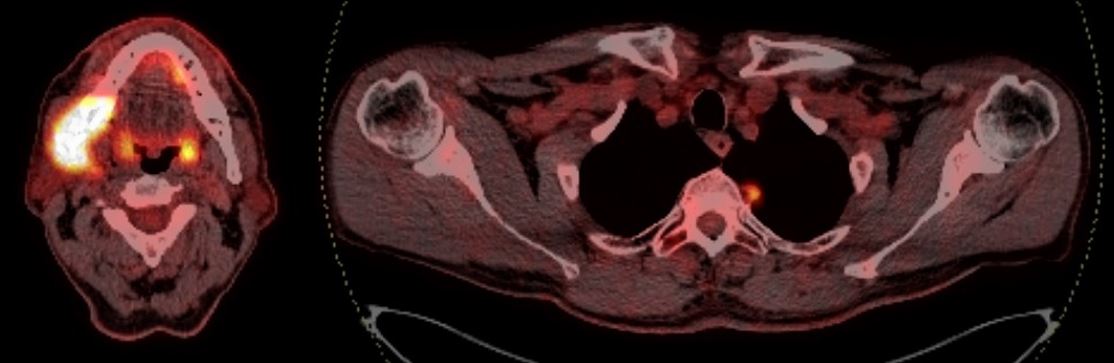

2. Рис. 2. ПЭТ/КТ с 18F-ФДГ (нивелирование образования щечной области справа с признаками репаративных процессов нижней челюсти, снижение метаболической активности лимфатических узлов шеи, накопление РФП в проекции образования верхушки левого легкого). Примечание: рисунок выполнен авторами | |